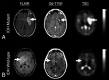

Sodium MR imaging has the potential to complement routine proton MR imaging examinations with the goal of improving diagnosis, disease characterization, and clinical monitoring in neurologic diseases. In the past, the utility and exploration of sodium MR imaging as a valuable clinical tool have been limited due to the extremely low MR signal, but with recent improvements in imaging techniques and hardware, sodium MR imaging is on the verge of becoming clinically realistic for conditions that include brain tumors, ischemic stroke, and epilepsy. In this review, we briefly describe the fundamental physics of sodium MR imaging tailored to the neuroradiologist, focusing on the basics necessary to understand factors that play into making sodium MR imaging feasible for clinical settings and describing current controversies in the field. We will also discuss the current state of the field and the potential future clinical uses of sodium MR imaging in the diagnosis, phenotyping, and therapeutic monitoring in neurologic diseases.